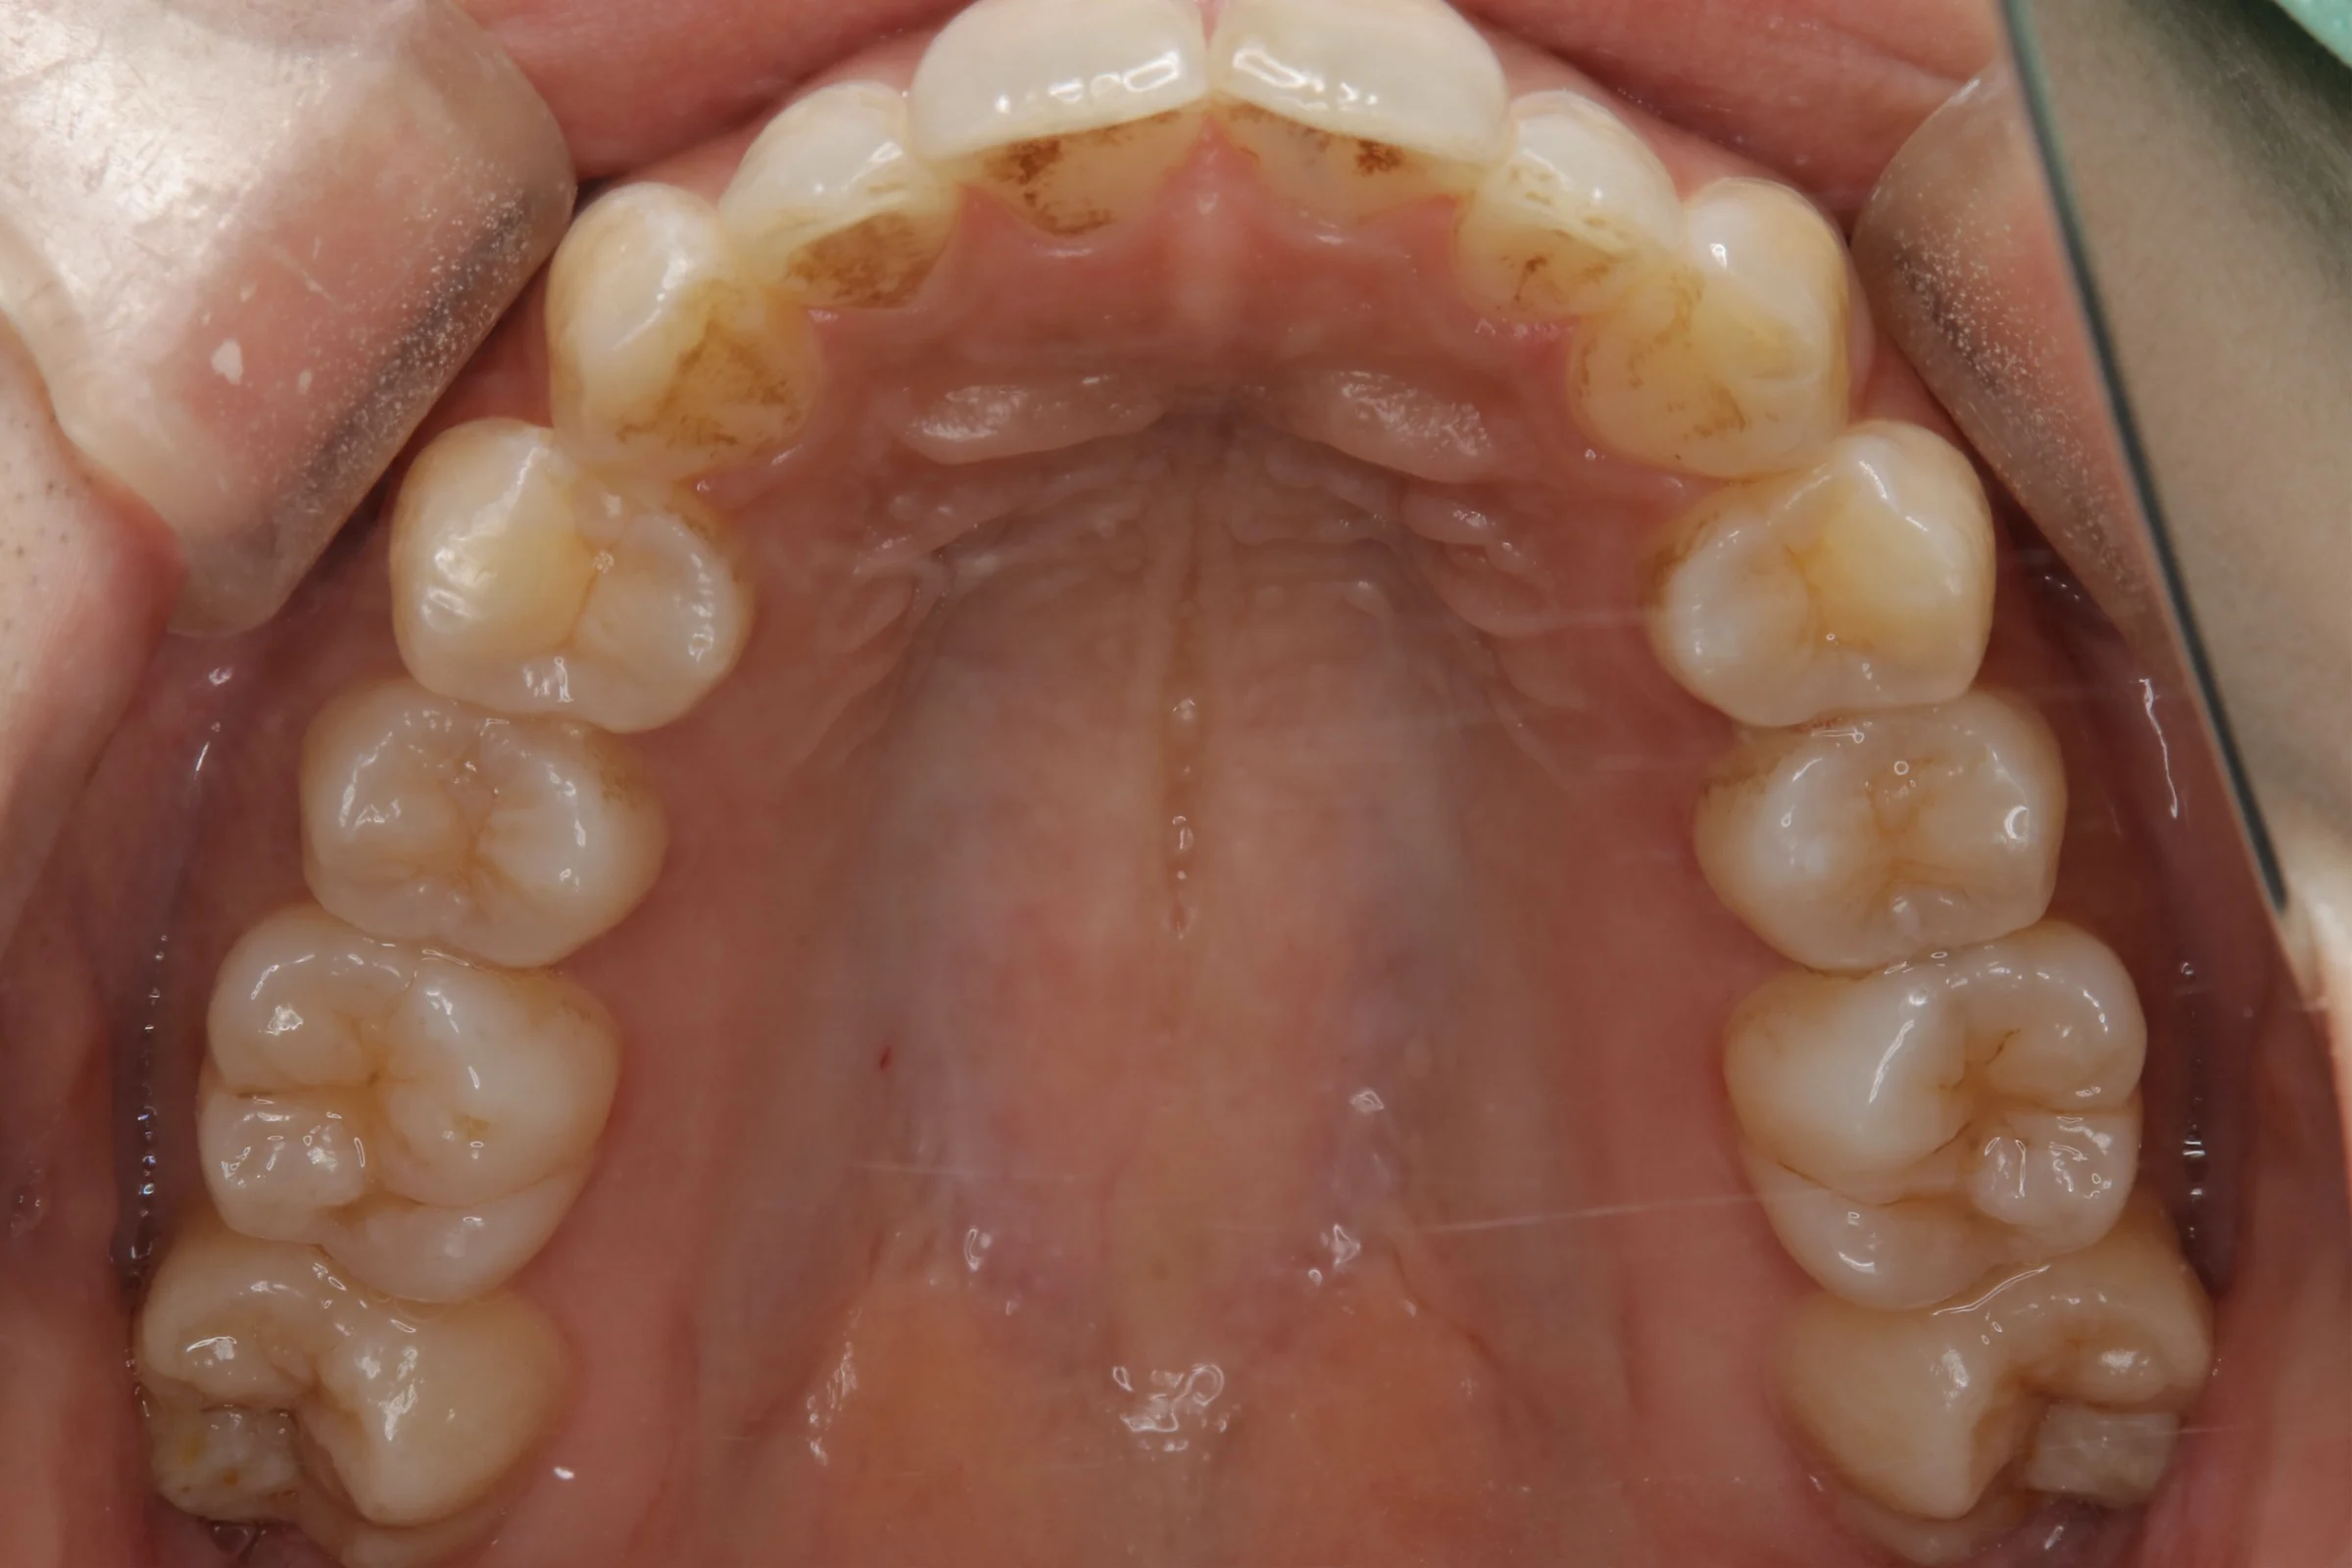

下の前歯の凸凹が気になる、上前歯2本が出ている感じも治したいということで来院された患者様です。

初診時

終了時